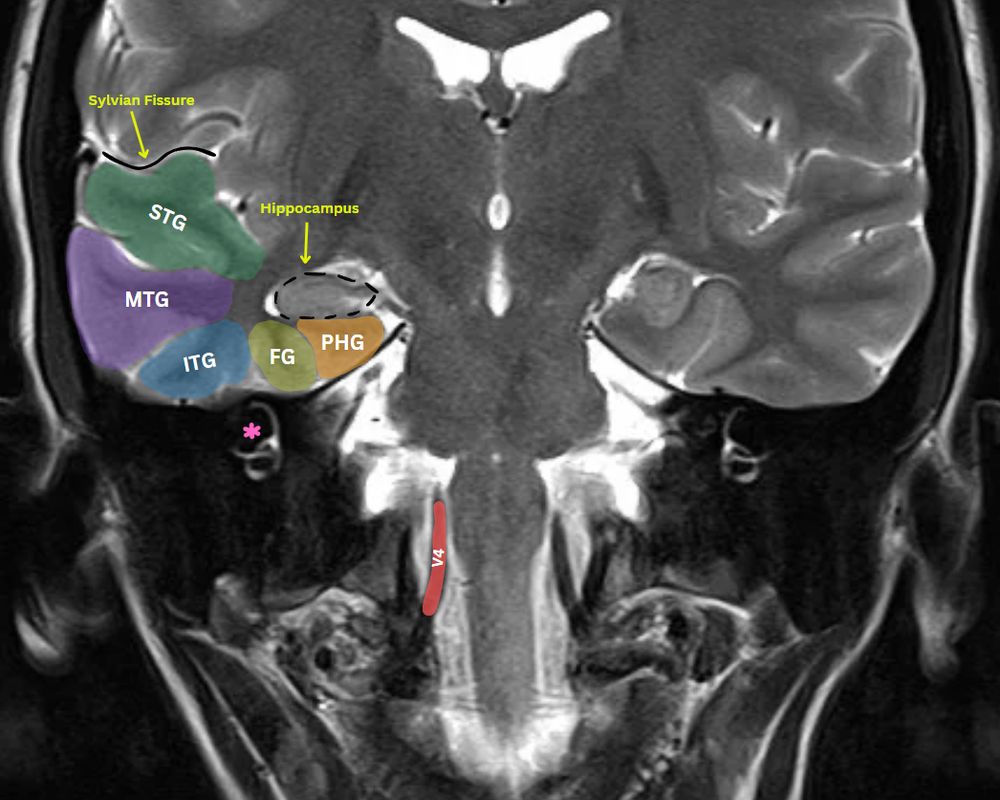

MRI Neuroanatomy

Superior temporal gyrus STG

Middle temporal gyrus MTG

Inferior temporal gyrus ITG

Fusiform gyrus FG

Parahippocampal gyrus PHG

Vertebral artery (red)-intradural segment

Semicircular canals (asterisk)

Trace these on the other side!

#RadSky #Radiology #Tech #science #neuro #AI